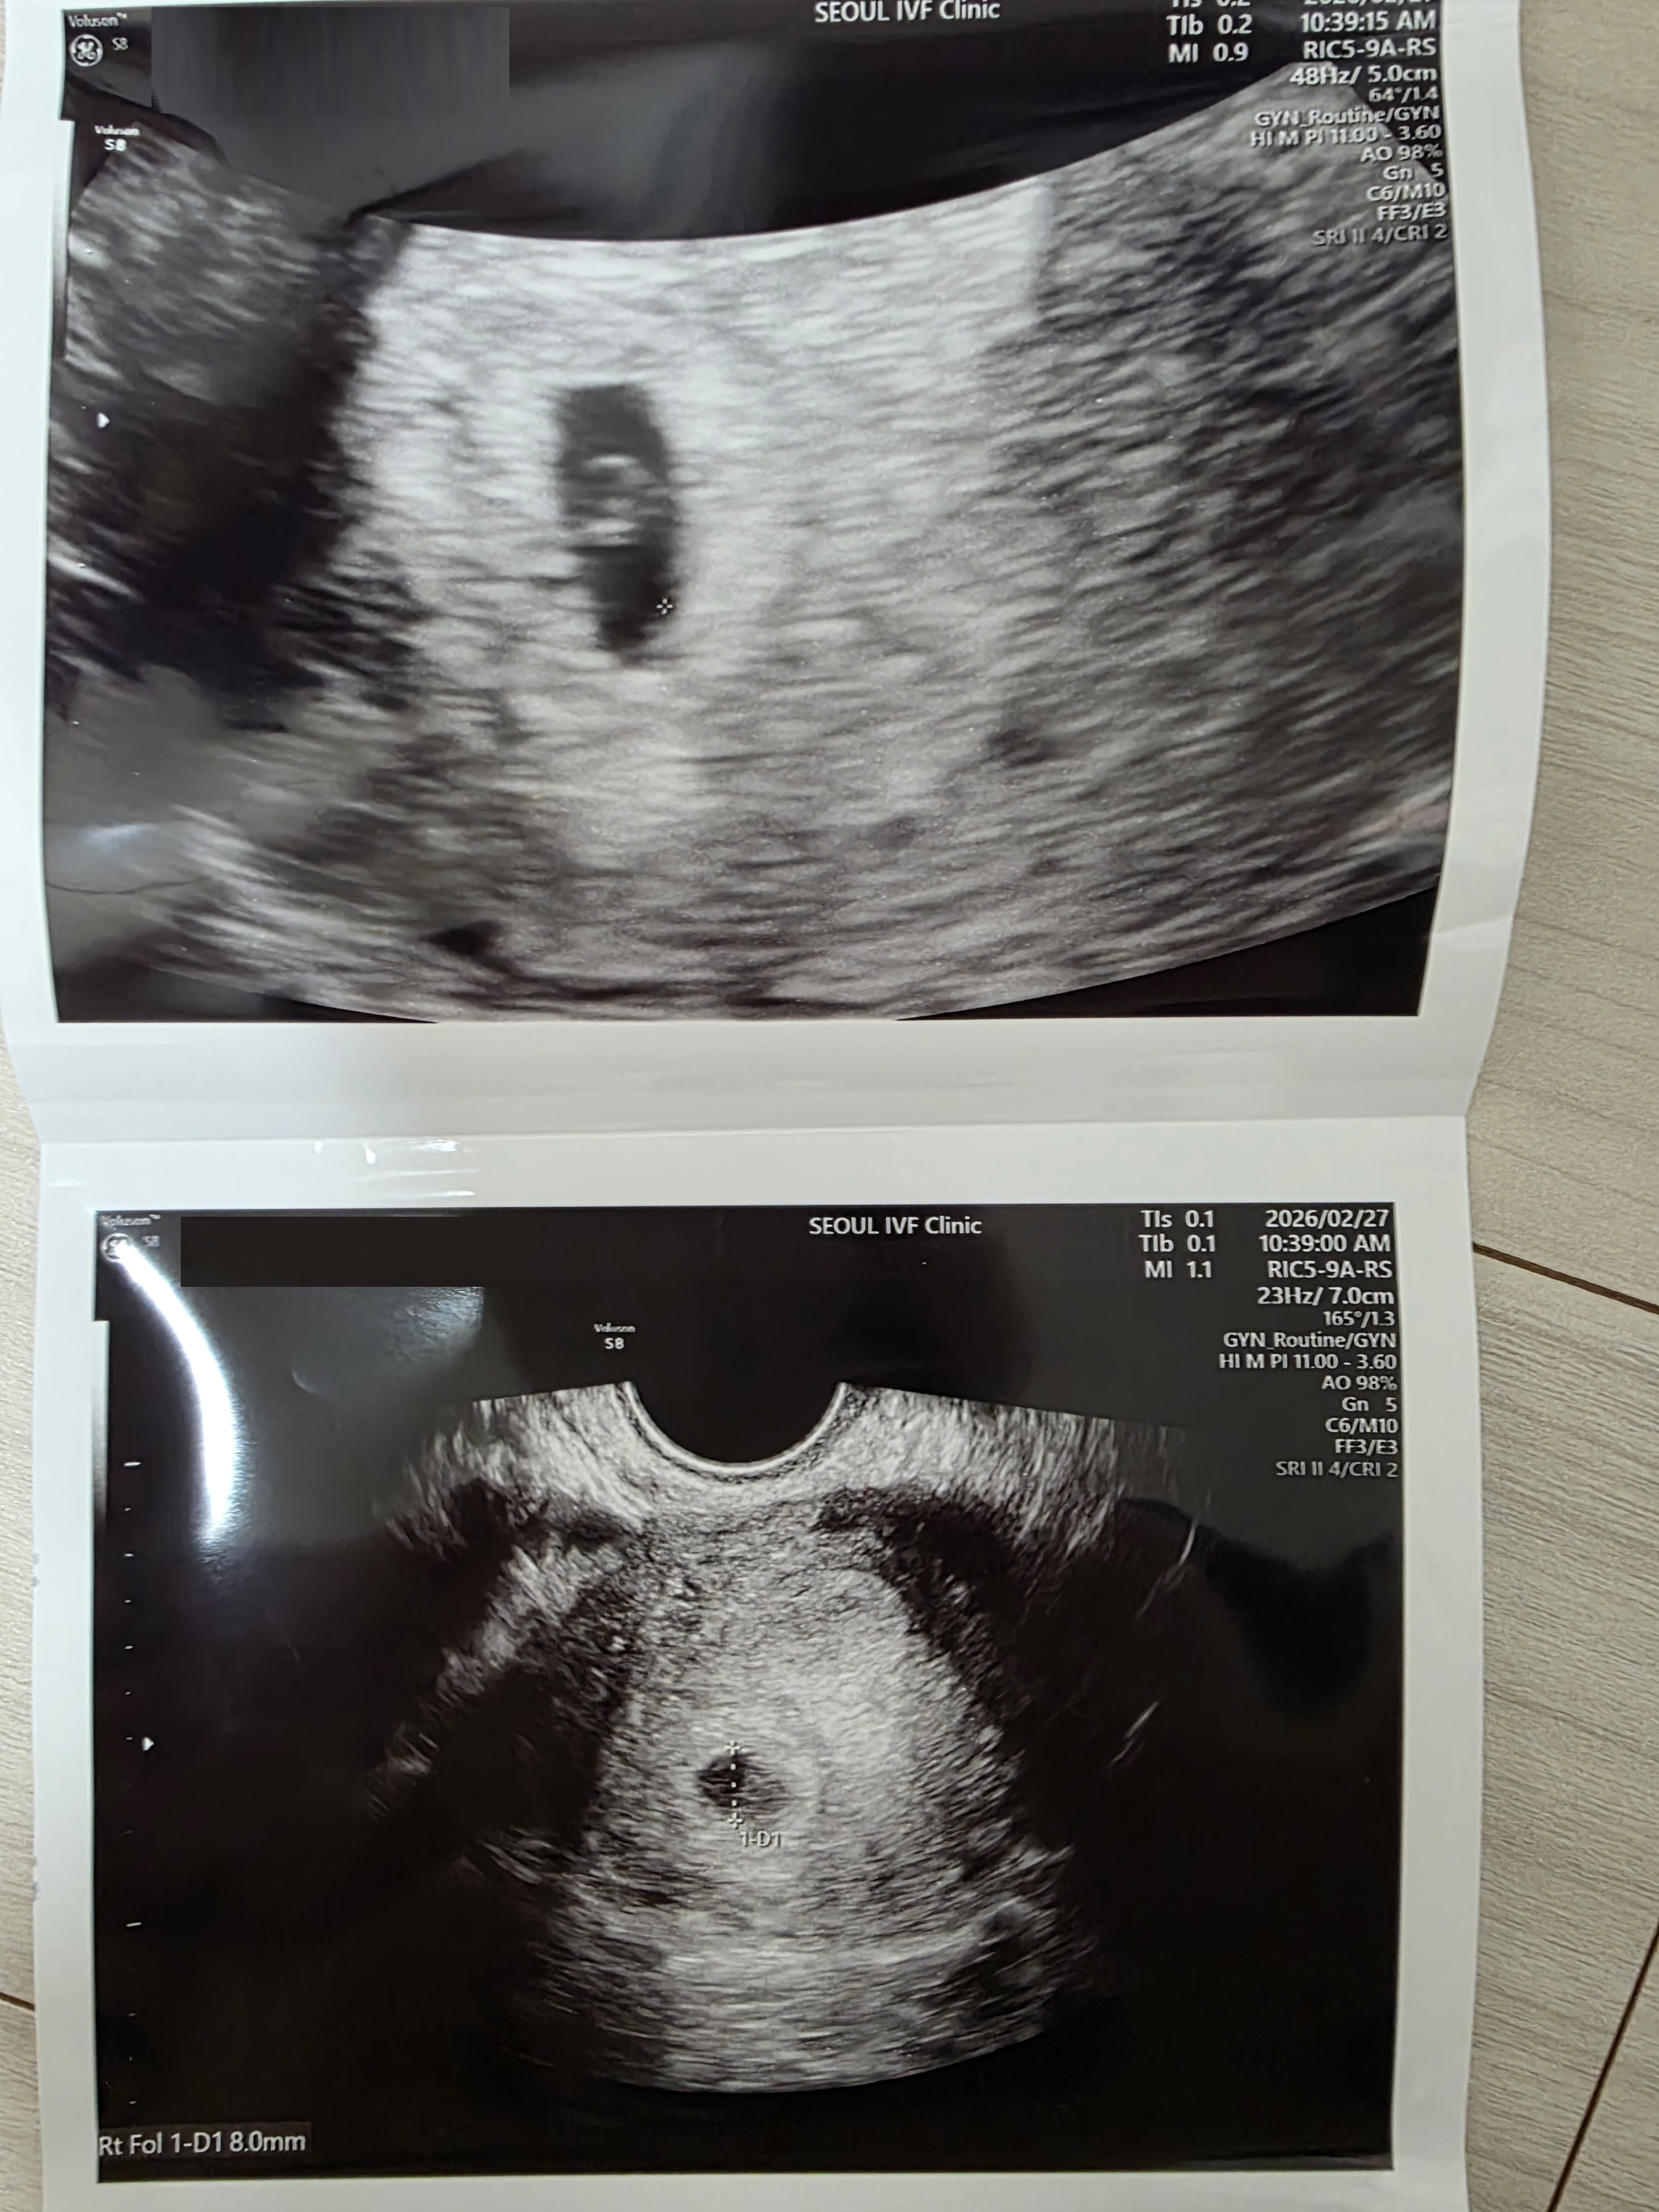

또 화학적 임신이라고 생각했는데… - 희망나눔